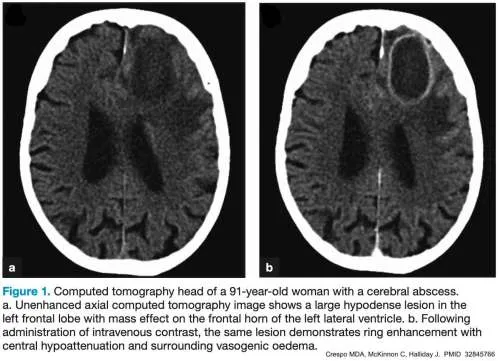

- Brain Abscess

- Predisposing: Otitis, sinusitis, dental sepsis, CHD.

- Classic triad (often incomplete <50%): Fever, headache, focal deficits.

- Imaging: Ring-enhancing lesion on CT/MRI.

- Rx: IV antibiotics +/- surgical drainage.